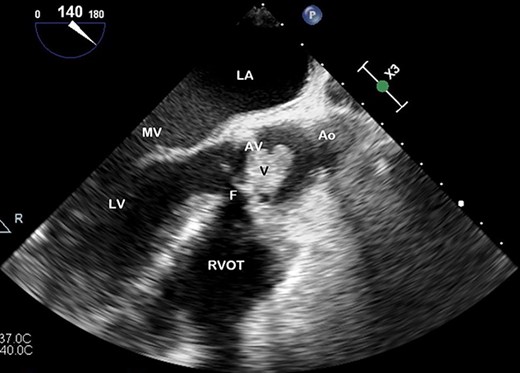

The patient’s electrocardiogram demonstrated a prolonged PR interval, non-specific anterior ST changes and inferior T-wave inversion. Though the chest X-ray was unremarkable, concurrently elevated inflammatory markers urged empiric antibiotic commencement. Computed tomography imaging demonstrated hyperdensity in the subarachnoid space overlying the right cerebral hemisphere. The clinical suspicion of endocarditis prompted a transoesophageal echocardiogram (TOE), demonstrating multiple vegetations on the prosthetic aortic valve (AV) and features suggestive of a paravalvular abscess (Figs 1 and 2). Splenic and bilateral renal infarcts were confirmed. Multiple sets of blood cultures isolated E. cloacae and intravenous meropenem was commenced.

TOE, long axis demonstrating a vegetation (V) on the AV obstructing the left ventricular outflow tract; Ao, aorta; F, fistula; LV, left ventricle; MV, mitral valve.